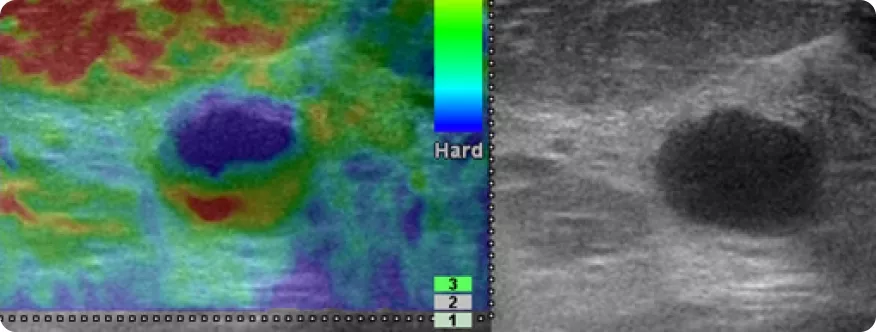

Image

Эластография/эластометрия

Эластография/эластометрия (определение жёсткости выявленных объектов относительно окружающей ткани молочной железы и определение площади выявленных объектов), УЗИ с внутривенным введением контрастного средства для ультразвукового исследования — являются дополнительными методиками УЗИ, которые проводятся по показаниям.